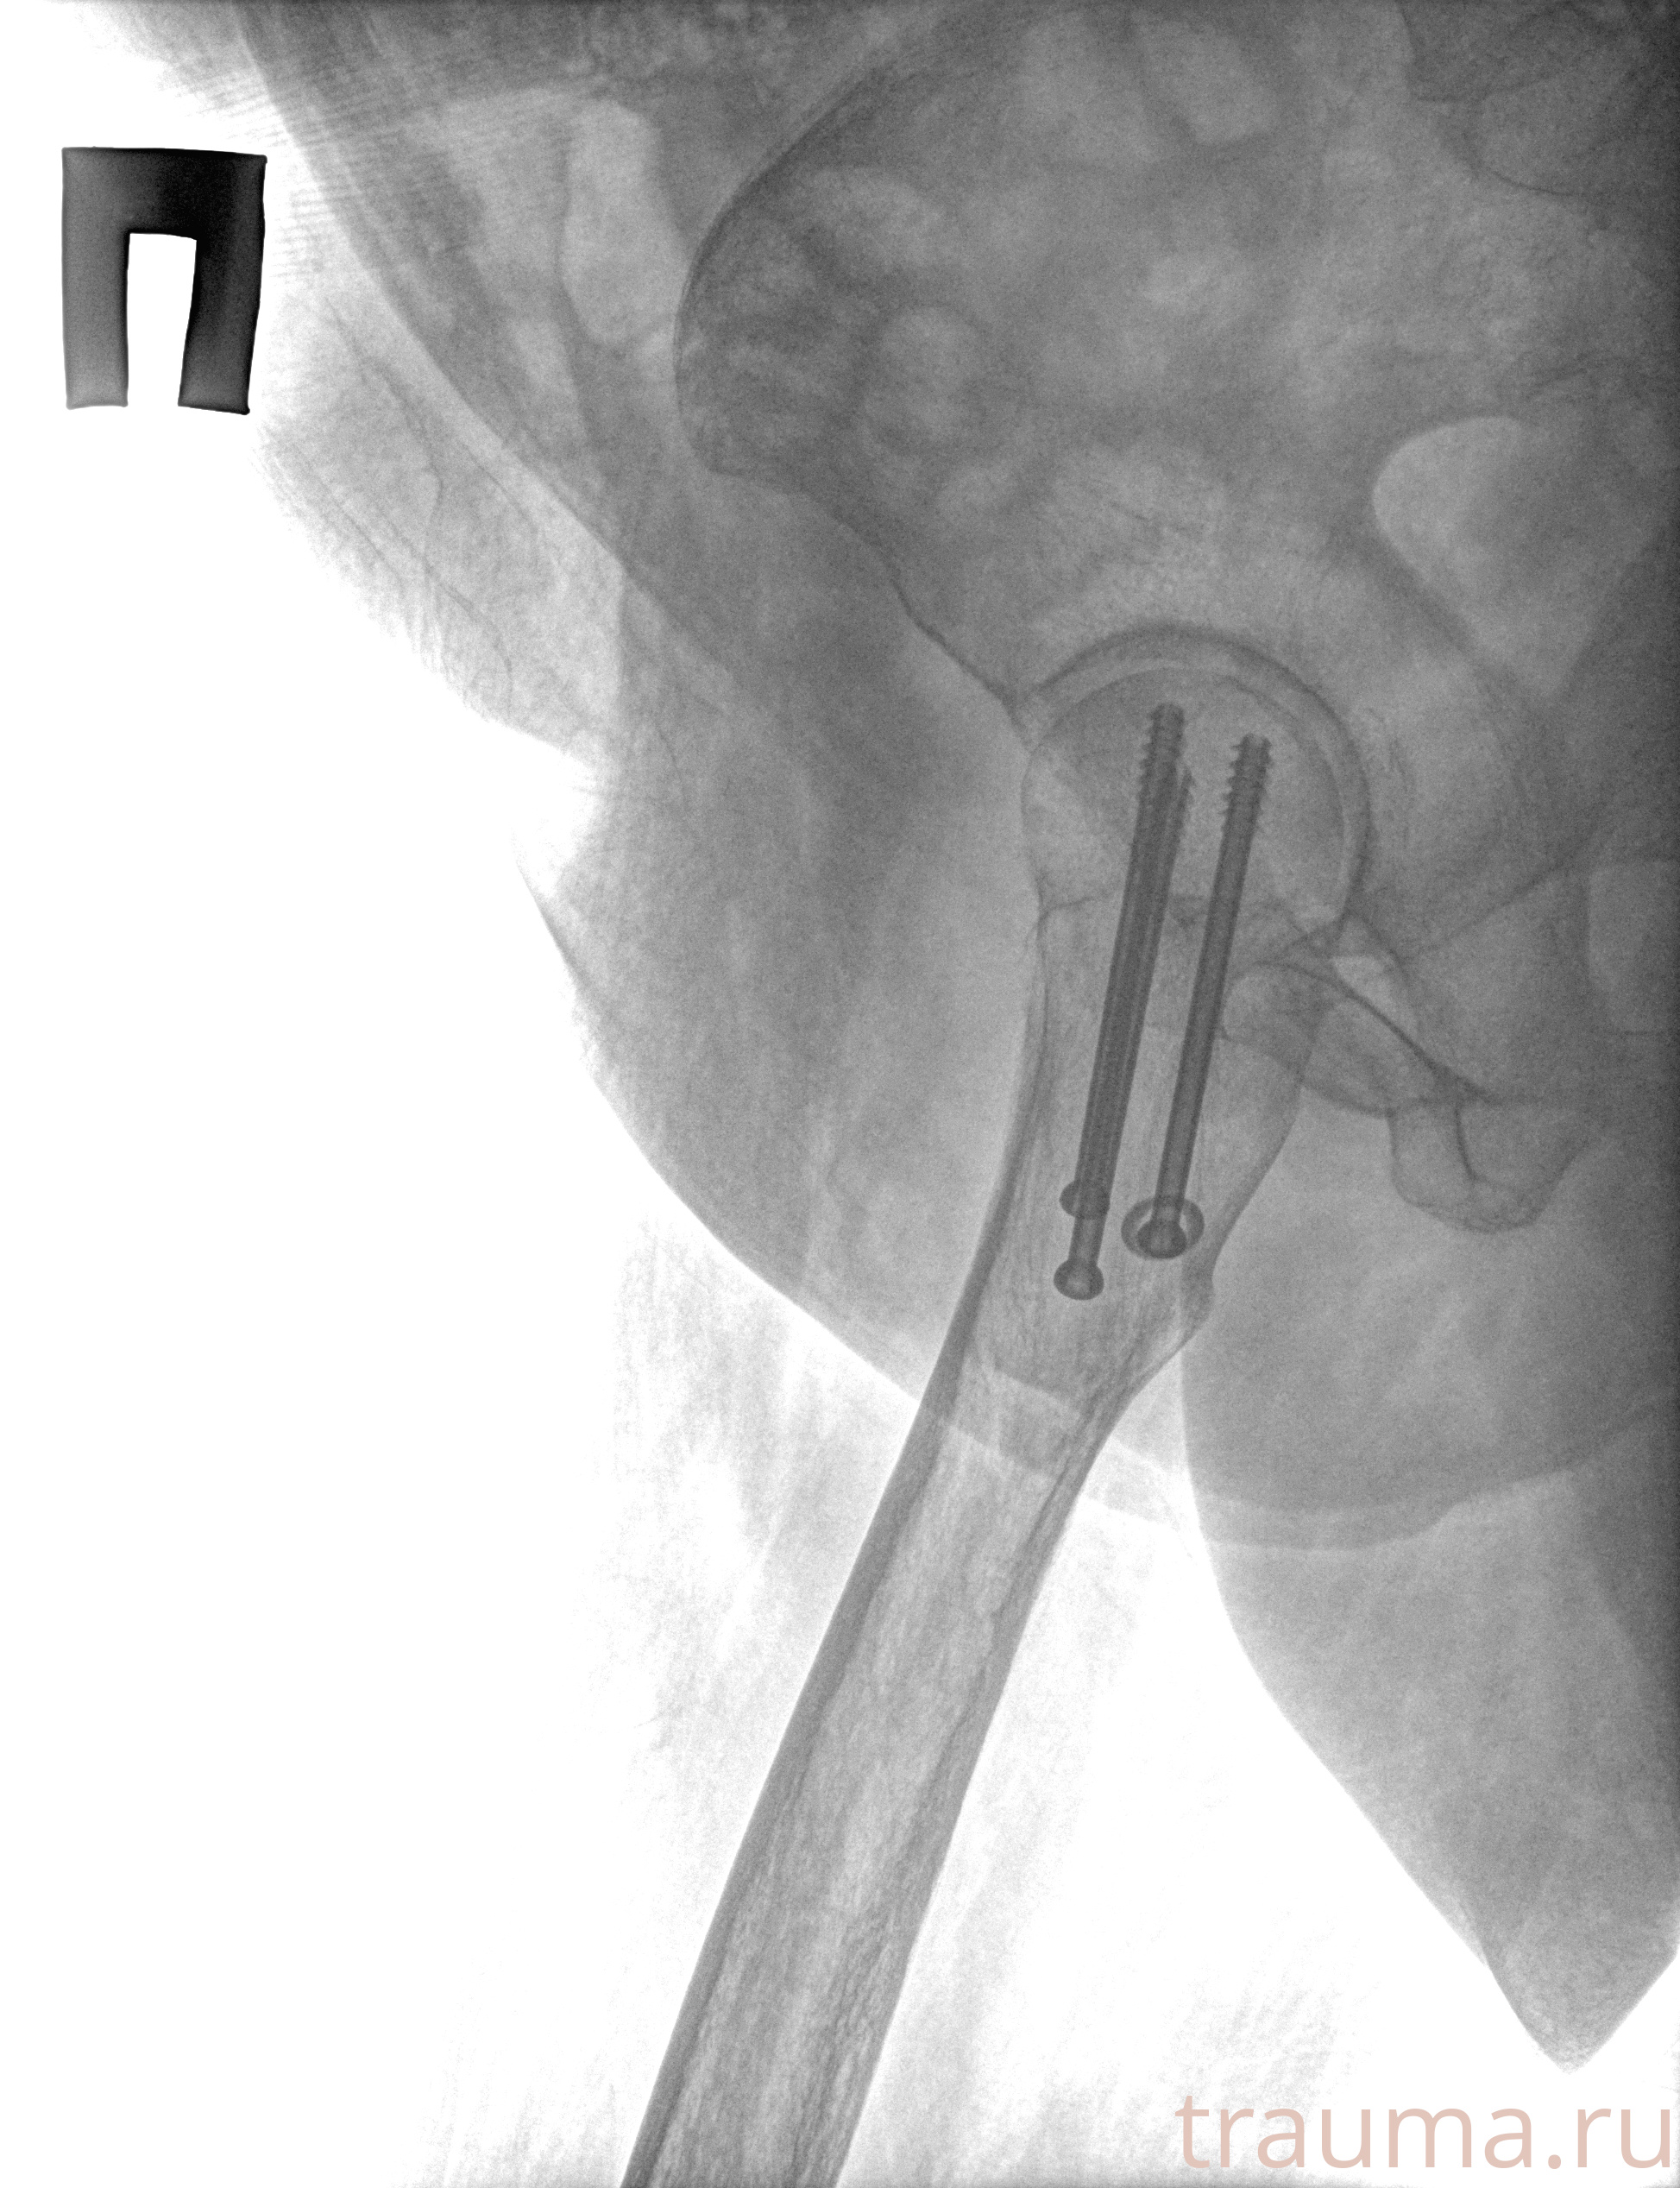

Рентгенограммы

Рентген на дому: по вашему адресу приезжает врач-рентгенолог, травматолог-ортопед с мобильным рентгеновским аппаратом, проводит диагностику травмы или заболевания, делает необходимые рентгенограммы, дает рекомендации по дальнейшему лечению. Получить качественные снимки в домашних условиях возможно благодаря уникальной методике, разработанной МосРентген Центром для института  Склифосовского